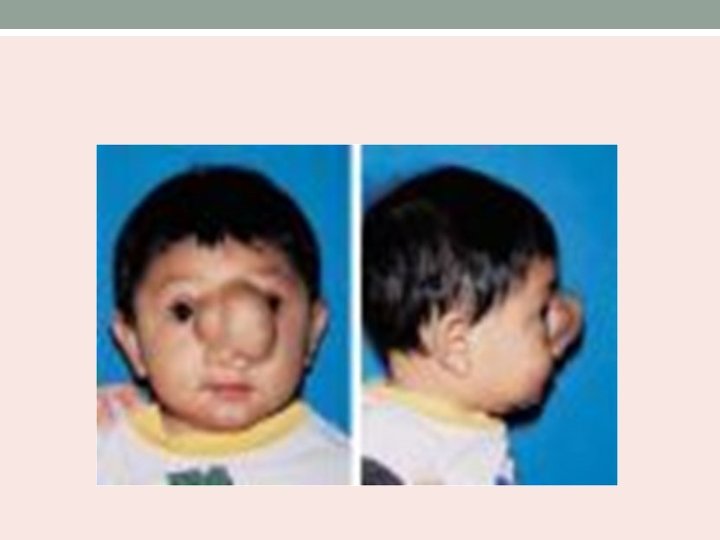

• Soft, cystic, bluish, compressible and translucent mass • Positive Furstenberg test. • Investigation – HRCT with contrast enhanced axial and coronal images. MRI to identify intracranial connection.